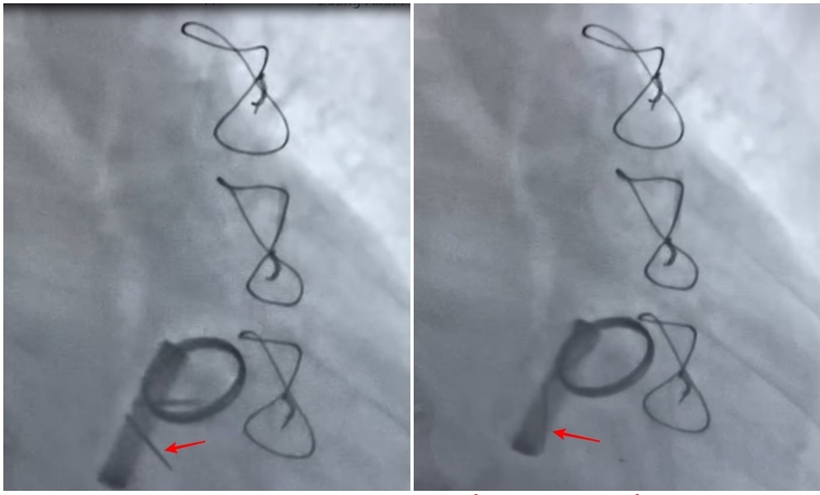

| Hình ảnh lá van cơ học đóng - mở tốt sau khi tiêu sợi huyết. Ảnh: BVCC |

Trước tình trạng nguy cấp, kíp bác sĩ Khoa Tim mạch do ThS.BS Ngô Văn Tuấn – Trưởng khoa chủ trì đã hội chẩn khẩn, quyết định sử dụng liệu pháp tiêu sợi huyết thay vì phẫu thuật tim mở lại. Sau 6 giờ điều trị, huyết khối tan hoàn toàn, van tim hoạt động bình thường, bệnh nhân hồi phục tốt, thoát khỏi nguy cơ mổ tim lần hai.